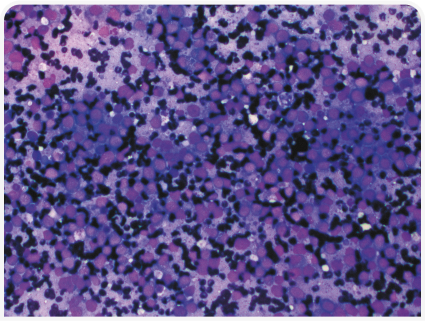

Цитологическое исследование ткани печени особенно важно при наличии многоочаговых или диффузных метаболических или опухолевых поражений (например, при круглоклеточной опухоли, вакуолярных гепатопатиях) (Рисунок 4). Его чувствительность по сравнению с гистопатологическим исследованием низкая; тем не менее этот метод диагностики быстрый, минимально инвазивный и безопасный, поэтому я во многих случаях рекомендую применять его в качестве первого инвазивного исследования ткани печени. Еще один полезный минимально инвазивный метод, редко сопровождающийся осложнениями, – холецистоцентез под контролем ультразвукового исследования (14).